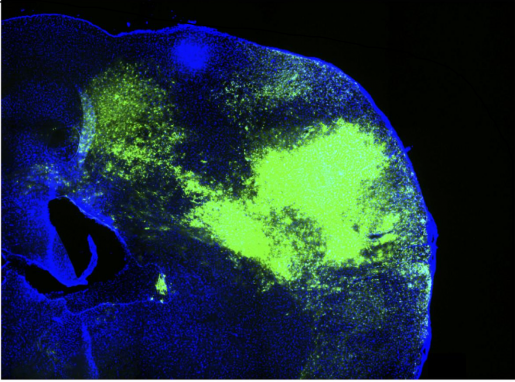

Brain tumors trigger silencing of neuronal activity

Sudden episodes of confusion and seizures often are the first signs of a malignant brain tumor. Using glioma mouse models, researchers detected waves of ultra-slow depolarization arising from the tumor margin. In the current study, researchers detected the depolarizing waves earlier than previously found, during a reproducible progression of inhibitory cell loss, glutamate dysregulation and inflammation in the tumor margin, and found that this excitability progressed more slowly when the tumor grew in a host brain that is genetically resistant to seizures.

Like a mastermind of its own destiny, glioma sets a stage that favors its own growth

BCM researchers and colleagues uncovered evidence about how glioma manipulates its environment in ways that favor its own growth. This research, published in Nature, suggests new strategies to treat patients with this condition, one of the most aggressive malignant primary brain tumors.